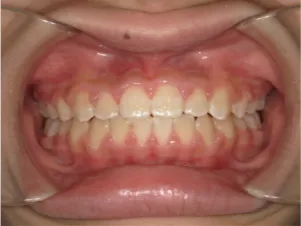

治療前①小5:生え変わり後期のため顔の成長を促進させる目的で拡大装置(アーチ形態の修正)と上顎前歯をそろえることを先行し、できるだけ非抜歯治療で進める予定を提案しました

| はじめのご相談 | 凸凹を治したい、治療方法を知りたい。 |

| カウンセリング・診断結果 | 治療方法は精密検査、分析をして検討することをご理解いただき、矯正治療で抜歯をするかしないかの違いについて説明し治療を希望されたので精密検査を行いました。 精検の結果、顔立ちは下顎が後退したタイプの出っ歯(下顎後退型上顎前突)でV-shaped arch(歯列が狭い)、凸凹、八重歯になっていて、機能的にはべろのポジションが悪い低位舌があります。 口元は問題ありません。 |

| 行ったご提案・診断内容 | 生え変わりが終わってなくマルチブラケット法による咬合治療には早い時期のため、顔立ちの成長を促す目的で歯列弓(アーチ)の拡大と前歯を並べながら永久歯が生えるのを待ち、咬合治療開始時に再診断で抜歯、非抜歯を最終検討する提案をしました。 再診断時(写真②)、歯列の拡大と上顎前歯の並べ替えはされていましたが八重歯となったため抜歯、非抜歯を検討しました。 口元は特に問題がなく非抜歯で八重歯を改善するためのスペースを作ることが可能なため非抜歯治療を提案しました。 治療は、 ・拡大および上顎左右6を遠心移動させてスペースを作る 予定装置 |